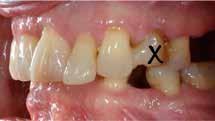

Patienttilfælde 1 (Fig. 1) er en 37-årig kvinde, henvist efter succesfuld behandling af stadie 3-parodontitis. Der er nu sundt

Før behandling

parodontium, ingen pocher over 4 mm, og både blødnings- og plakindeks er under 10 %. Patienten er motiveret for ortodontisk behandling, da hendes tænder er vandret over tid, delvist som følge af reduceret parodontium.

Der ses anterior trangstilling i begge kæber og overerupterede 1+1 og 2,1-1,2, hvilket resulterer i dybt bid med 2- tæt på ganepåbidning. Der er normale sidetandsrelationer, men der ses 5 mm horisontalt overbid (HOB) og 7 mm vertikalt

overbid (VOB). Papillen mellem 1+1 er betydeligt reduceret pga. fæstetab, og de mesialt kippede 1+1 har resulteret i en ”dark triangle”. Den facioorale funktion er for nuværende i.a. Panoramarøntgen (Fig. 1, I) viser marginalt knogletab i begge kæber og fravær af 8,7+7,8 og 8,7-8.

Objektivt anbefales behandling af det dybe bid, som ubehandlet forventes at forværres yderligere over tid. Patienten har ønske om behandling med æstetisk ortodontisk apparatur, alignere, og det vurderes muligt at behandle malokklusionen med alignere. Dog anbefales det generelt, at alignere undgås eller benyttes med væsentlige modifikationer af alignerens retention ved tandmobilitet, da dette ellers kan medføre jiggling, når aligneren tages af og på mange gange dagligt. På den anden side er der nogen evidens for, at alignerbehandling er associeret med bedre renhold og parodontal sundhed sammenlignet med fast apparatur (16).

Der planlægges alignerbehandling af begge kæber med intrusion af 1+1 og 2,1-1,2, nivellering af trangstilling UK med interproksimal reduktion (IPR) (Fig. 2 A, B) og senere IPR OK for reduktion af dark triangles mellem incisiverne efter nivellering. Patienten instrueres i at benytte alignere 20-22 timer/ dag med alignerskift hver 7. dag, og patienten ses hver 3.-8. uge under forløbet. Den første alignerserie består af 16 alignere for nivellering OK/UK og IPR i UK (Fig. 2). Efter denne serie planlægges IPR mellem incisiverne i OK for reduktion af dark triangles (Fig. 3) samt yderligere intrusion af OK og UK-fronten i 12 refinement-alignere. Patienten udviser god kooperation og er meget tilfreds med alignerapparaturet, som er mindre synligt end det faste apparatur (Fig. 4).